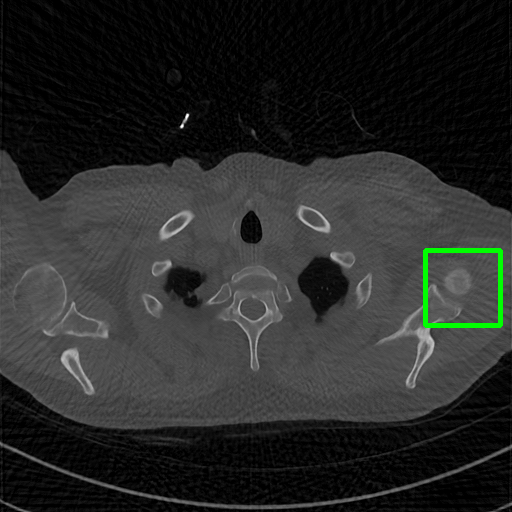

Generalizablity on COVID-19 dataset. Finally, we use slices of another patient in the COVID-19 dataset to test the generalizability of trained models, and quantitative performances are compared in Table 4. ImgTrans and DuDoTrans have achieved a larger improvement about 4-5 dB over CNN-based methods, which shows that the long-range dependency modeling ability helps capture the intrinsic global property of general CT images. Further, our DuDoTrans exceeds ImgTrans about 0.4 dB in all cases, even larger than the original NIH-AAPM dataset. The improvement ensures that DuDoTrans generalizes well to out-of-distribution CT images. Besides, we also show the visualization images in Fig. 5 when = 96. Coinciding with the quantitative comparison, our DuDoTrans show better reconstruction on both global patterns and local details.

Ground Truth

FBP

FBPConvNet

DuDoNet

ImgTrans

DuDoTrans